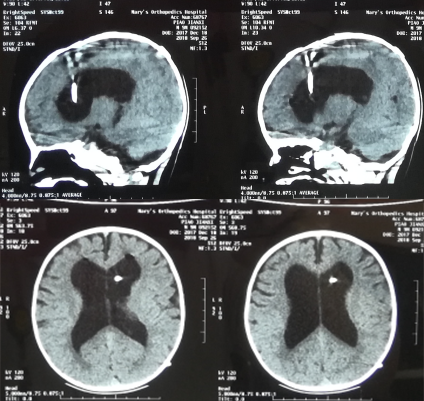

入院当天进行了脑室外引流术,术后第1天即2018年7月29日,查头颅CT示脑室引流术状态(图-4)。

图-4:2018年7月29日头颅CT

引流术后15天即2018年8月13日,眼球内聚“对眼”减轻,呕吐减少,查头颅CT示脑室缩小(图-5)。

图-5:2018年8月13日头颅CT

引流术后50天即28天即2018年9月17日,查头颅CT示脑室进一步缩小(图-7)。

图-7:2018年9月17日头颅CT

脑脊液各项化验均正常后,于2018年9月26日进行了脑室腹腔分流术,术后当天复查头颅CT示脑室分流术后状态(图-8)。

图-8:2018年9月26日头颅CT